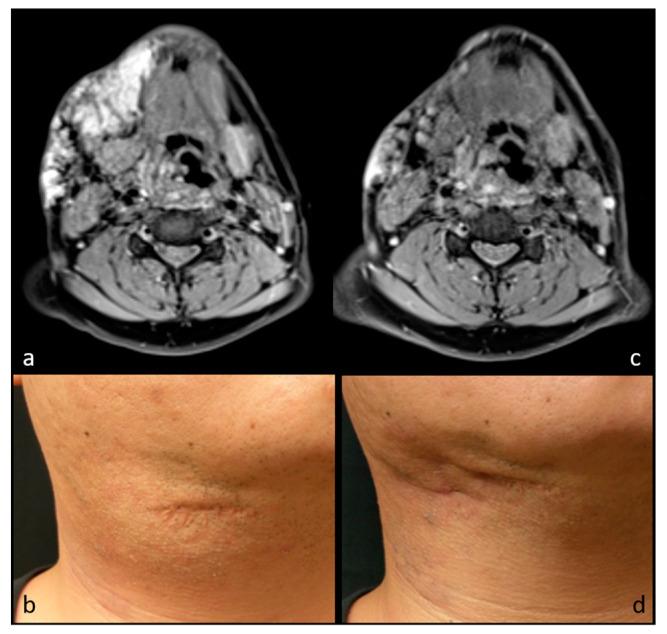

: To evaluate the effectiveness of radiofrequency ablation (RFA) using the moving-shot technique for benign soft tissue neoplasm. : This retrospective study reviewed eight patients with benign soft tissue neoplasm presenting with cosmetic concerns and/or symptomatic issues who refused surgery. Six patients had vascular malformation, including four with venous malformation and two with congenital hemangioma. The other two patients had neurofibroma. All patients underwent RFA using the moving-shot technique. Imaging and clinical follow-up were performed in all patients. Follow-up image modalities included ultrasound (US), computed tomography (CT), and magnetic resonance (MR) imaging. The volume reduction ratio (VRR), cosmetic scale (CS), and complications were evaluated. : Among the seven patients having received single-stage RFA, there were significant volume reductions between baseline (33.3 ± 21.2 cm), midterm follow-up (5.1 ± 3.8 cm, = 0.020), and final follow-up (3.6 ± 1.4 cm, = 0.022) volumes. The VRR was 84.5 ± 9.2% at final follow-up. There were also significant improvements in the CS (from 3.71 to 1.57, = 0.017). The remaining patient, in the process of a scheduled two-stage RFA, had a 33.8% VRR after the first RFA. The overall VRR among the eight patients was 77.5%. No complications or re-growth of the targeted lesions were noted during the follow-up period. Of the eight patients, two received RFA under local anesthesia, while the other six patients were under general anesthesia. : RFA using the moving-shot technique is an effective, safe, and minimally invasive treatment for benign soft tissue neoplasms, achieving mass volume reduction within 6 months and significant esthetic improvement, either with local anesthesia or with general anesthesia under certain conditions.

这项回顾性研究纳入了 8 名因美容需求和/或症状而拒绝手术的良性软组织肿瘤患者。6 名患者为血管畸形,包括 4 例静脉畸形和 2 例先天性血管瘤。另外 2 例患者为神经纤维瘤。所有患者均采用移动射击技术行 RFA。所有患者均进行了影像学和临床随访。随访的影像学方式包括超声(US)、计算机断层扫描(CT)和磁共振成像(MR)。评估了体积减少率(VRR)、美容评分(CS)和并发症。

在接受单阶段 RFA 的 7 名患者中,基线(33.3±21.2cm)、中期随访(5.1±3.8cm,P=0.020)和最终随访(3.6±1.4cm,P=0.022)的体积均有显著减少。最终随访时的 VRR 为 84.5±9.2%。CS 也有显著改善(从 3.71 降至 1.57,P=0.017)。正在接受预定两阶段 RFA 的 1 名患者,在第一次 RFA 后 VRR 为 33.8%。8 名患者的总体 VRR 为 77.5%。在随访期间,未发现靶向病变有并发症或复发。8 名患者中,2 名在局部麻醉下接受 RFA,其余 6 名在全身麻醉下接受 RFA。